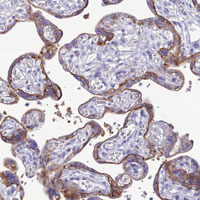

- Immunohistochemical staining of human placenta with CRB2 polyclonal antibody (Cat # PAB28149) shows strong membranous and cytoplasmic positivity in trophoblastic cells at 1:50-1:200 dilution.

- Immunohistochemistry (Formalin/PFA-fixed paraffin-embedded sections)